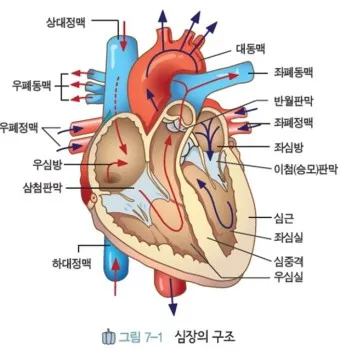

1. 심장 관련 원인

- 부정맥: 정상 심박수 범위 60-100회/분 이탈

- 심장 판막 이상: 증상 발현 시 심박수 변동 20% 이상

- 빈맥증: 휴식 시에도 심박수 100회/분 이상

- 서맥증: 심박수 60회/분 이하로 저하